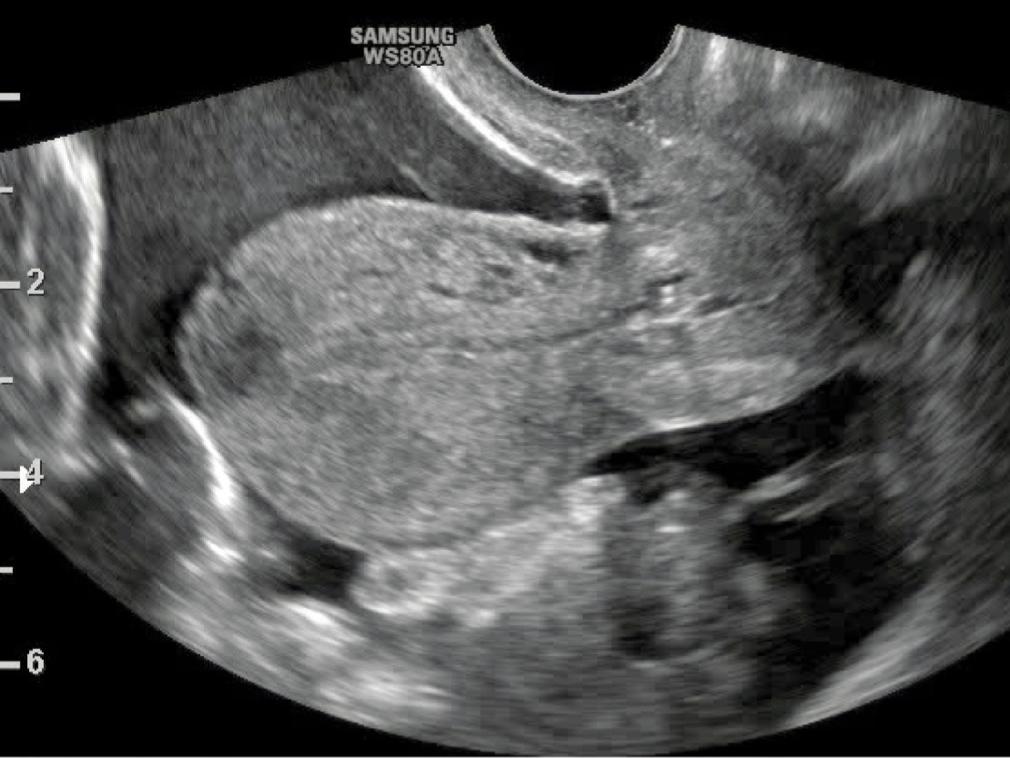

Fig. 2.

TVS of a patient diagnosed with EP shows a large amount of free fluid. Not eligible for MTX therapy